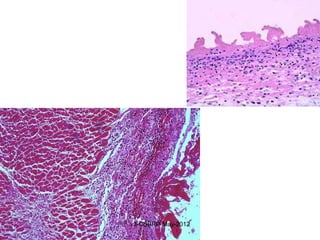

Suppurative inflammation

FIGURE 2-20 Purulent inflammation. A, Multiple bacterial

abscesses in the lung, in a case of bronchopneumonia. B, The

abscess contains neutrophils and cellular debris, and is surrounded

by congested blood vessels.v3-CSBRP-May-2012

Morphologic Patterns ofAcute Inflammation 1. SEROUS INFLAMMATION 2. FIBRINOUS INFLAMMATION 3. Suppurative inflammation: Abscess  Characterized by large amounts of PUS:  PMNs, Necrotic tissue  Edema fluid  Bacteria  Abscess: Localized collections of purulent inflammatory tissue  Histologically:  Central core of necrotic tissue  Viable leucocytes at the periphery  Wall composed of granulation tissue  Walled off by fibrocollagenous tissue v3-CSBRP-May-2012

Suppurative inflammation FIGURE 2-20Purulent inflammation. A, Multiple bacterial abscesses in the lung, in a case of bronchopneumonia. B, The abscess contains neutrophils and cellular debris, and is surrounded by congested blood vessels.v3-CSBRP-May-2012